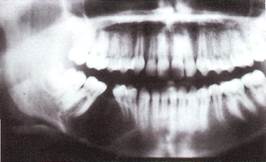

Рентгенологическая картина, характеризуется нарушением кортикального слоя, отсутствие выраженной границы опухоли, может содержать постоянные зубы или их зачатки. В других случаях на рентгено­грамме видны полости с довольно четкими кон­турами, подобно кистозным образованиям.